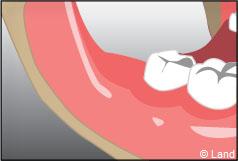

Les extractions simples sont accomplies sur des dents qui sont visibles en bouche, qui ne sont pas endommagées excessivement par la carie et qui peuvent être extraites sans complication. L’extraction peut être considérée comme une désinsertion de la dent de son alvéole. Elle se fait en général à l’aide d’un davier (pince) après une anesthésie locale.

Une vérification est entreprise pour ne pas oublier un éventuel résidu radiculaire, des fragments osseux et pour cureter éventuellement les tissus infectés.

Le saignement sera contrôlé en mettant une compresse de coton sur le site de l’extraction et en fermant la bouche pour créer une pression.

Pour préserver le caillot en formation, il ne faut pas boire du côté de la zone extraite ni cracher pendant une dizaine d’heures.

La perte du caillot risque d’entrainer une infection osseuse douloureuse appelée alvéolite.